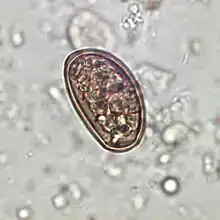

Traditionally, diagnosis for dicrocoeliasis infection involves the identification of Dicrocoelium dendriticum eggs in the faeces of a human or other animal. However, in humans, eggs in the stool may be a result of ingesting raw infected animal liver and may not in fact indicate dicrocoeliasis.[9] Therefore, examining bile or duodenal fluid for eggs is a more accurate diagnostic technique in combination with a liver-free diet.[6]